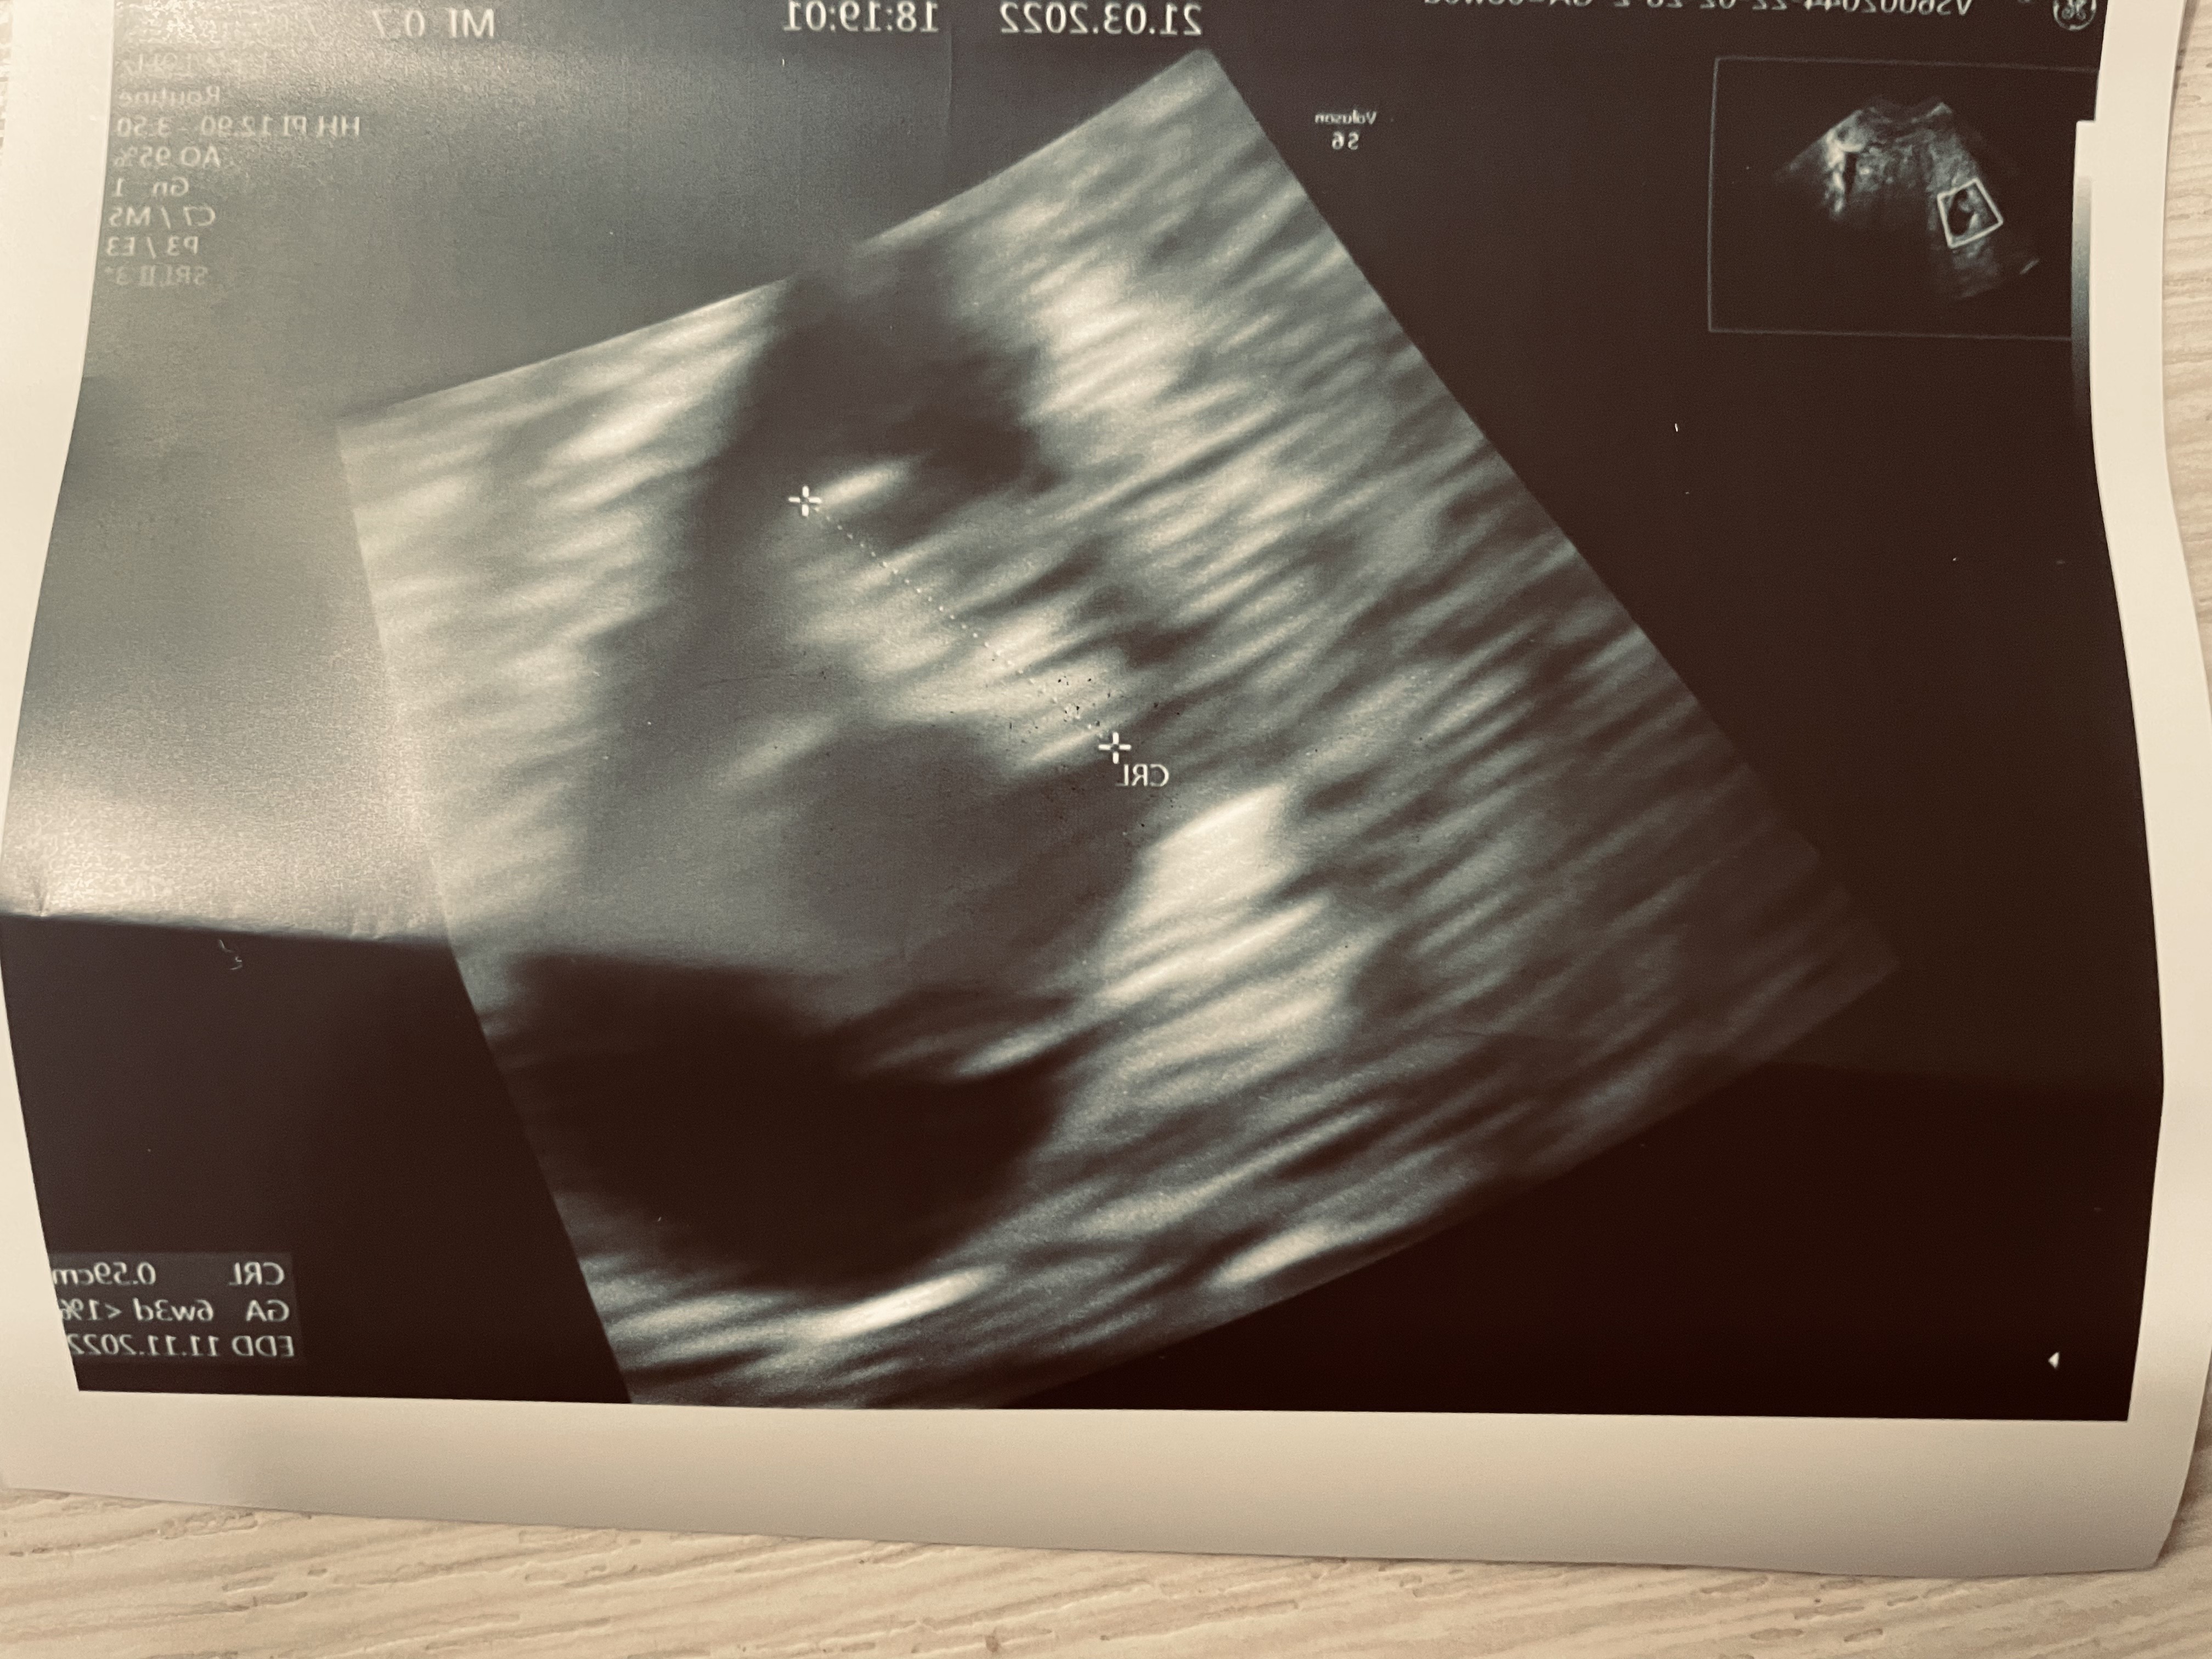

Byłam właśnie na usg! 😍 Ciąża wygląda w porządku, 8mm, 5+4 tc (wg aplikacji i ostatniej miesiączki 6+2), dobrze umiejscowiona, tylko oczywiście wczesna i mam wrócić za półtorej tygodnia 😂🙈👀. Jestem chociaż o tyle spokojna, że jest wszystko teraz w porządku 💪🏻❤️.